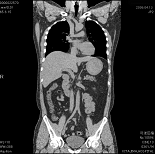

平成18年4月16日より、従来のシングル・ヘリカルCTからマルチスライス・ヘリカルCTに機種変更をしました。MDCTでは、 X線管球が身体の回りを1回転している間に極めて沢山の画像データを収集することができます。身体の中の詳細な構造を観察するためには、スライス(断面)の厚さを薄くする 必要がありますが、そうすると逆に止めなどの検査時間が膨大なものとなってしまい、従来は不可能な方法となっていました。しかしMDCTになったことにより、なんと10秒程度の 息止め1回で例えば肺などの全域を撮影できるようになりました。

その結果、単に画像が速く綺麗に撮れるということにとどまらず、従来はできなかった縦方向の画像(実際に撮影しているのではなく、 検査後にコンピュータで計算させて上下方向の画像を作成するもの:MPR(画像という)や、立体的な3次元画像なども従来よりもはるかに有用なものとして活用できるように なっております。また高知県内では限られた病院施設にした導入されていない最新悦の高機能CTです。当院ではこのCTを使用することにより、患者様に対してより正確でより 迅速な検査を提供することを目指しています。